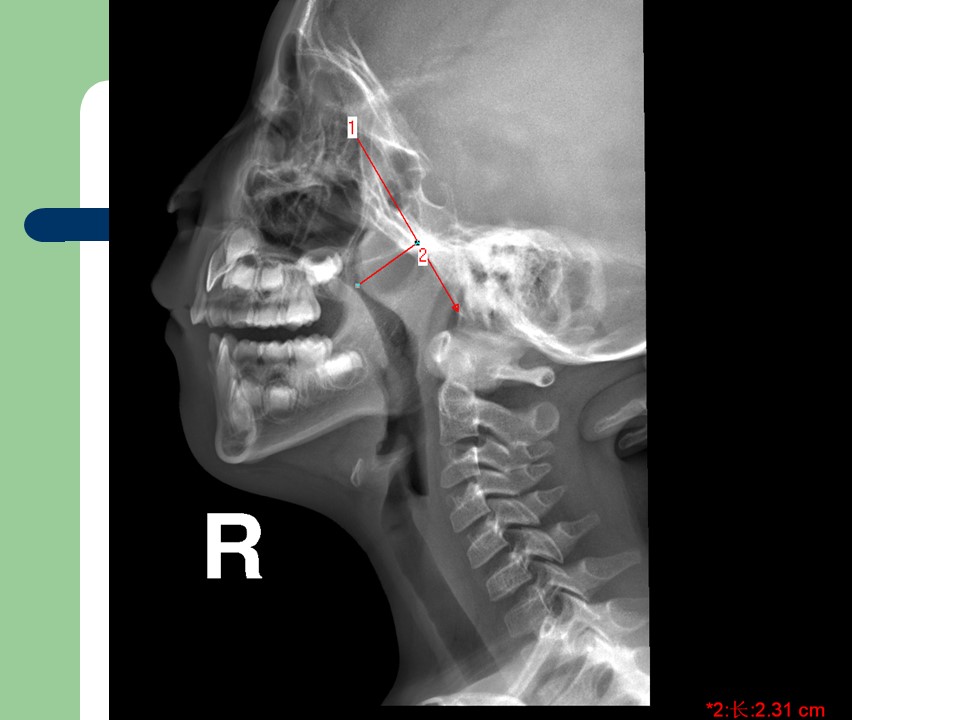

“腺样体增大的X线测量与诊断” 的相关文章